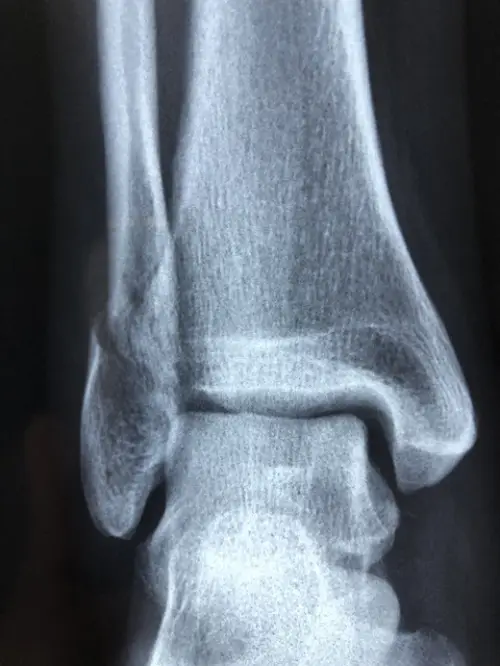

발목 접질림, 즉 발목 염좌는 말 그대로 발목을 지탱하는 인대가 갑작스럽게 늘어나거나 부분적으로 파열되는 상태를 말합니다. 흔히 스포츠 활동 중이나 일상생활에서 흔히 경험하는 부상이지만, 그 심각성은 결코 가볍게 넘길 수 없습니다. 많은 경우 발바닥이 안쪽으로 꺾이면서 외측 인대가 손상되는데, 전체 발목 염좌 중 약 85%를 차지할 만큼 매우 흔하게 발생하는 패턴입니다.

발목 염좌는 손상 정도에 따라 크게 세 가지 등급으로 분류됩니다. 가벼운 1단계는 인대가 미세하게 손상된 상태로, 약한 통증이나 거의 없는 붓기와 함께 보행이 가능합니다. 2단계는 인대가 부분적으로 파열되어 통증과 부종, 멍이 나타나 보행이 어렵고, 3단계는 인대가 완전히 파열된 상태로 극심한 통증과 부종이 나타나며 발을 딛는 것조차 힘듭니다.

발목을 접질렀을 때 손상의 정도는 다양하며 그에 따른 회복 기간도 크게 차이가 납니다. 발목 염좌는 인대 손상의 심각도에 따라 1단계에서 3단계로 분류할 수 있는데, 각각의 단계에 따라 증상과 치료 방법, 회복 시간이 달라집니다. 정확한 분류를 이해하는 것은 적절한 치료 계획을 세우고 부상을 더 악화시키지 않는 데 매우 중요합니다.